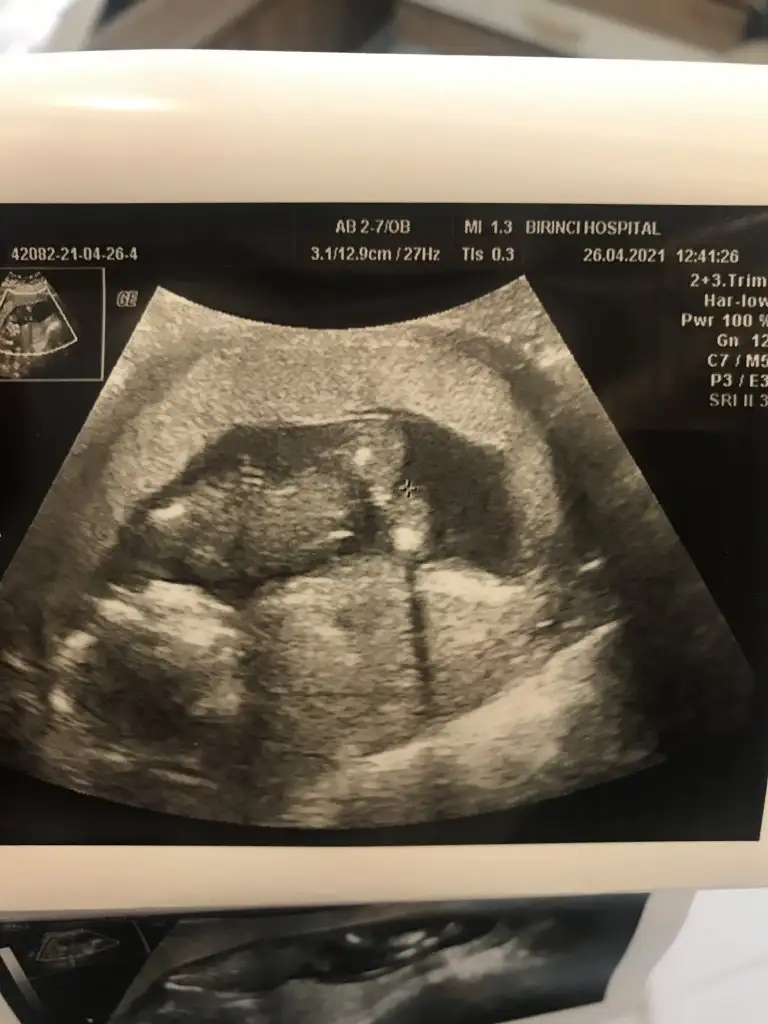

İlk ultrason resimlerinizi paylaşın ramzi teorisine göre cinsiyeti tahmin edeyim bakalım tutacak mı?

Ramzi teorisine göre cinsiyet tahmini yapacagim ilk ultrasyon resminizi atin bakiyim. Eger cinsiyetiniz belliyse hic söylemeeyin bakalm dogru tahmin edebilecekmiyim daha dogrusu ramzi teorisi hakli cikacak mi?